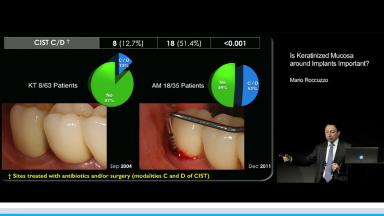

Patients with inadequate attached keratinized tissue often complain of pain and soreness when performing oral hygiene measures in comparison to patients with adequate keratinized tissue. Lack of keratinized tissue impedes proper oral hygiene leading to plaque accumulation, recession and compromised esthetics - even when patients present with good oral hygiene and are enrolled in a strict supportive and maintenance care program.

This presentation discusses recent studies showing that - although there are no minimum dimensional requirements - attached keratinized tissue is essential to facilitate oral hygiene measures and the long-term maintenance of implants.

- recognize the importance of adequate attached keratinized tissue around implants for long-term implant maintenance, functionality, and esthetics